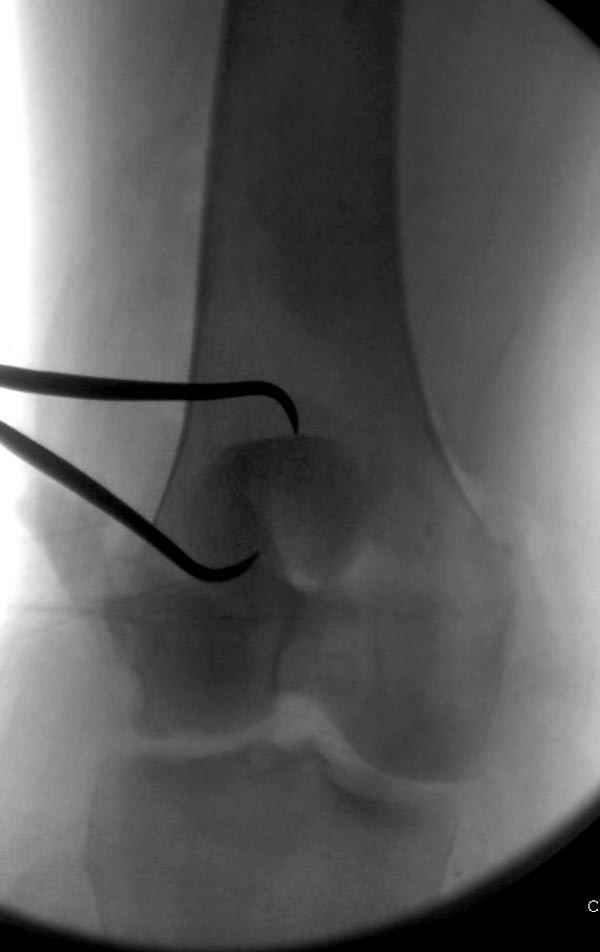

Сегодня досылаю остальные снимки, которые не прошли вчера. Как вчера писал, после фиксации перелома надколенника с дефектом кости и собственной связки, наложили ваккуум и наружный фиксатор. (снимки 4-9)

Внешний фиксатор держим около 6 недель, поэтому был выбран метод фиксации шурупами и еще линия перелома была диагональной, не было нужды в tension band technique, cannulated screws удобнее, провел спицы и по ним шурупы.

Почти все компании имеют стержни 3-4-5 мм в диаметре для наружного фиксатора и только одна 6 мм с hydroxyapatite покрытием. Стержни имеют различную заточку и self drilling, что связано с патентной проблемой каждой компании, Стержень проводим по двойному проводнику, после предварительного сверления меньшим диаметром сверла, 3.8мм при 5мм, стержень в диафизе предпочтительно провести вручную, за исключением метафиза, где используется дрель.

На слайдах (не четко обозначены бедро и голень): на бедре по наружно-передней поверхности, между вастус латералис и прямой головками, а на голени по передне-медиальной поверхности, желателен подбор длины резьбовой части стержня по ширине поперечника кости. На снимке: дистальное кольцо, метод проведения стержня через канюлю-проводник.